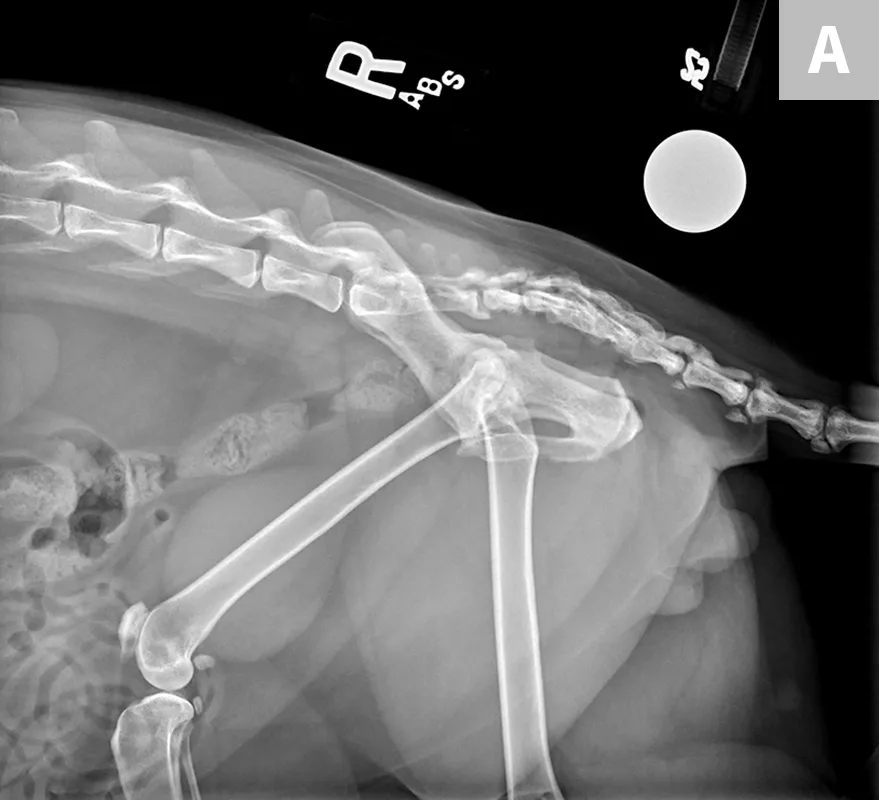

Josh weighed 15.9 lb (7.2 kg), 0.9 lb (0.4 kg) of which had been gained over the past 12 months. BCS was 7 out of 9 as compared with 6 out of 9 the previous year; sarcopenia was evident, particularly over hips and thighs (Figure 1). His coat looked unkempt.

Apparent muscle loss over the hips

Based on clinical and radiographic findings (Figures 3-6), degenerative joint disease (DJD) involving the hips and elbows bilaterally and the right stifle, with myofascial pain in the dorsolumbar area, was diagnosed.4

FIGURE 3

Lateral (A) and dorsoventral (B) views of the pelvis. Figure A shows a moderate amount of the smoothly marginated, bridging, bony proliferations surrounding the 2nd through 5th coccygeal vertebrae. A moderate amount of kyphosis is present on the tail, centered in the bony proliferation. A mild amount of irregularly marginated bony proliferation is present surrounding the facet joint of the C5-C6 intervertebral disk space. Figure B shows poor coverage of the right femoral head by the acetabulum. A moderate amount of irregularly marginated bony proliferation is present on the cranial and caudal aspects of the acetabulum and femoral neck. There is decreased soft tissue associated with the left pelvic limb as compared with the right. A small osteophyte on the left cranial acetabulum can be noted. Image courtesy of Dr. Karen Perry. Interpretation: Chronic, healed caudal vertebral fracture, C2-C4. Moderate, right coxofemoral osteoarthritis and mild left coxofemoral osteoarthritis